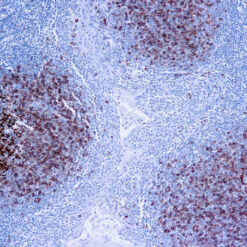

Calponin-1

Multiple isoelectric variants of calponin have been identified but only two molecular weight isoforms exist (34kDa and 29kDa). Expression of the 29kDa form, I-calponin, is primarily restricted to muscle of the urogenital tract, whereas the higher molecular weight variant has been demonstrated in vascular and visceral smooth muscle. Calponin is a calmodulin, F-actin and tropomyosin binding protein, which is thought to be involved in the regulation of smooth muscle contraction. Calponin expression is restricted to smooth muscle cells and has been shown to be a marker of the differentiated (contractile) phenotype of developing smooth muscle.

| Positive Control Tissue | Uterus |